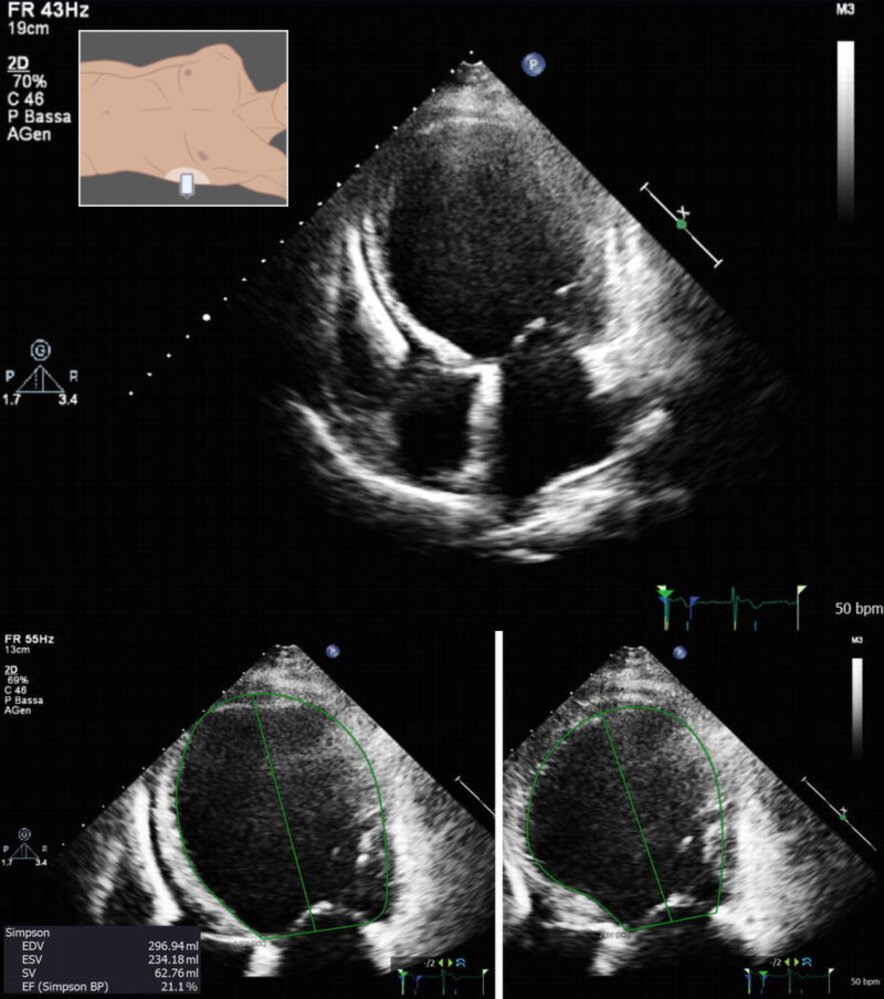

Echocardiography LV cavity size

• Significantly increased

EF

• Significantly decreased

• Left or biventricular dilation (with or without atrial dilation)

• Wall motion abnormalities

• Systolic dysfunction